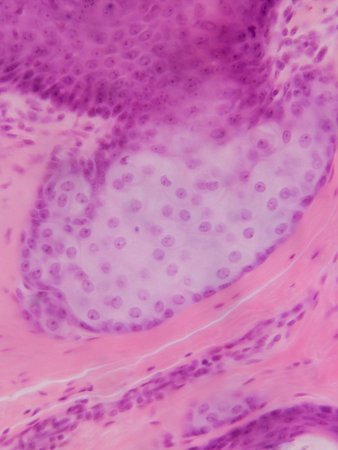

Squamous cell carcinoma diseased tissue under the microscope 100x

Bowen's Disease Tumor under the microscope 100x